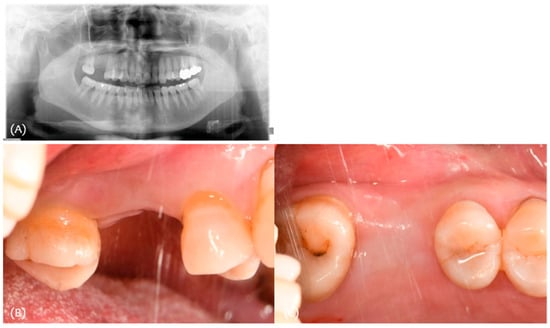

3.1. Case 1